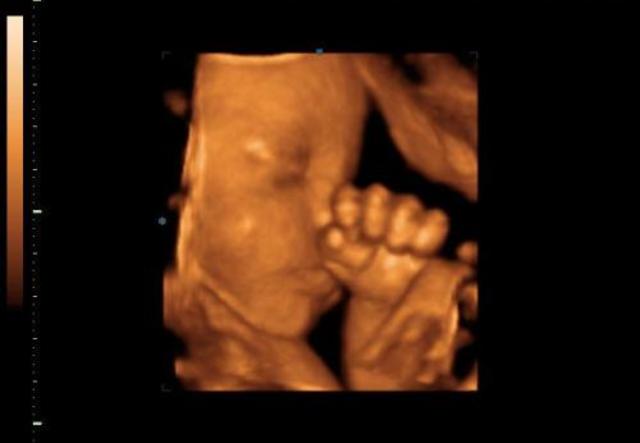

A negyedik hónapban baba már folyamatos mozgásban van, csontjai pedig egyre szilárdabbak, így egyre nagyobb az esély, hogy édesanyja is megérezze az apró rúgásokat.